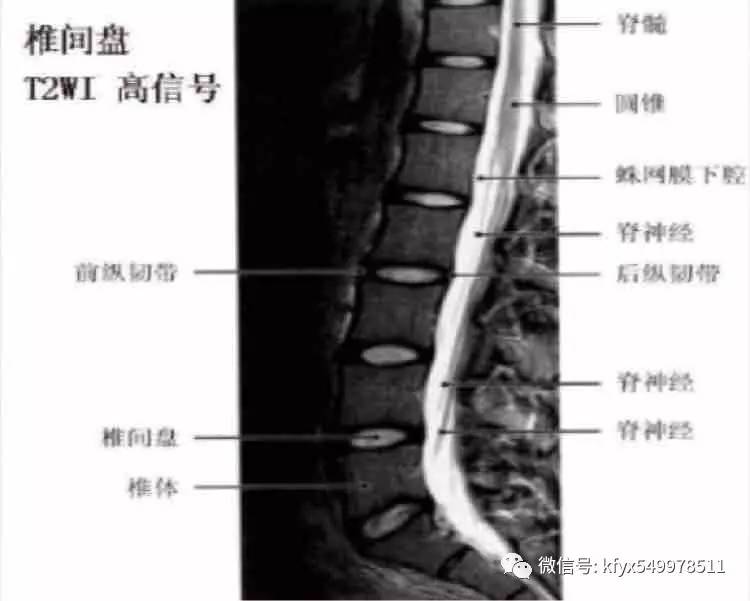

在矢状面图像上,椎体的前缘及后缘可见条状前纵韧带及后纵韧带,在T1加权像、T2加权像和部分翻转梯度回波图像上呈低信号。腰椎呈前凸曲度,椎体呈肾形,横径大于前后径,前缘凸,侧缘平,后缘凹,在T1加权像上为中等强度信号。椎弓根为椎体上方向后突的骨柱,构成椎间孔的上、下缘,在T1加权像上为中等强度信号。每个腰椎小关节面为透明软骨覆盖,厚2-4mm。

(2)椎间盘:腰椎椎间盘呈肾形,是由软骨终板、纤维环及髓核组成。软骨终板覆盖椎体上下面,在椎体与髓核之间。在SE席列T1加权像上,椎间盘中心部比周围部分信号强度略低,外周部分纤维环与前后纵韧带汇合处的信号更低。在T2加权像上信号强度恰好相反。纤维环和后纵韧带的信号相近,往往难以区分。髓核呈高信号。

(3)椎管内结构:①硬膜外间隙:硬膜外间隙系骨性椎管与硬脊膜之间的空隙,其内主要含脊神经、动脉、静脉、脂肪及少量结缔组织。腰椎的硬膜外间隙填充相当厚的硬膜外脂肪、韧带、神经和血管。硬膜外脂肪在T1及T2加权像上呈高信号强度。硬脊膜为致密纤维组织,在神经根平面外突,其内含有蛛网膜,共同构成神经根鞘。蛛网膜位于硬脊膜内面,二者之间有潜在的硬膜下隙。在MRI下,硬脊膜难与蛛网膜区分开,二者统称为鞘膜。②蛛网膜下隙:脊髓表面包绕软脊膜,软脊膜与蛛网膜之间为蛛网膜下隙。在MRI图像上见到的鞘膜囊内的脑脊液,实际是位于蛛网膜下隙的,脑脊液在T1加权图像上为低信号。在T2加权图像上信号高于脊髓。蛛网膜下隙在L2以下比较宽,由脑脊液填充,在T1加权像呈低信号强度,在L2加权像呈高信号强度,明显高于脊髓,因而脊髓结构可清晰显示。③脊髓马尾:脊髓位于蛛网膜下隙的中央.其末端为圆锥,圆锥的末端可在矢状面图像上清楚显示,止于L1,2平面。在T1加权像呈中等信号强度,在T2加权像信号强度比椎间盘和脑脊液低,为此二者易区分。脊髓的灰质与白质的MRI信号亦有不同,在横断面T1加权图像上,中央灰质是H形高信号,而周围白质信号较低。脊髓圆锥向下移行为纤维性终丝。终丝的信号强度类似或低于脊髓信号。约5%的正常人终丝内含有不同量的脂肪,信号明显增高。在圆锥平面向下走行的腰骶神经根称作马尾。马尾神经由上至下逐渐变少。旁正中矢状位显示神经根呈扇形从后上向前下方向延伸。④神经根的信号强度较低,但在脂肪组织的衬托下仍然十分清楚。静脉及静脉丛仍为低信号。大部分韧带为胶原纤维组织,在T1、T2加权图像上及部分翻转梯度回波图像上为低信号,黄韧带内含大量弹性纤维,故在T1 、T2加权图像上为中等强度信号。